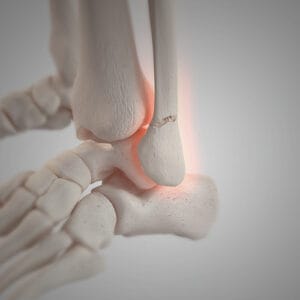

prelomi skočnog zgloba